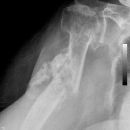

Schulterluxation